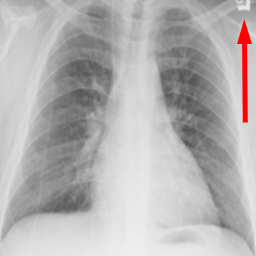

Research is based on the second update of the "COVID-19 Radiography Database" Chowdhury et al. (2020); Rahman et al. (2021); Cov (2022) developed by a team of researchers from Qatar University, Doha, Qatar, and the University of Dhaka, Bangladesh along with their collaborators from Pakistan and Malaysia in collaboration with medical doctors. The database incorporates posterior-to-anterior (AP)/anterior-to-posterior (PA) chest X-ray images from multiple public sources Vayá et al. (2020); Winther et al. (2020); SIR (2020); Cohen et al. (2020a, b); Haghanifar et al. (2022); RSN (2018); Kermany et al. (2018) and contains: 3616 images of COVID-19-positive cases, 6012 images of lung opacity (non-COVID lung infection), 1345 images of viral pneumonia, 10192 images of healthy lungs. Images are provided after conversion to common PNG format with 256x256 dimensions. For each image, the dataset authors provided a corresponding lung segmentation mask obtained using a dedicated U-Net model Rahman et al. (2021). Sample images from the database are presented in Fig. 2.

Many images in the dataset contain annotations or marks made during the image acquisition or afterwards by a radiologist. Examples of such images are presented in Fig. 3. Such symbols in the training dataset are known to generate biases as classifiers tend to target their attention to the presence of the symbols instead of genuine features of the image Rajaraman and Antani (2020); DeGrave et al. (2021). Therefore after the initial preprocessing, consisting of cropping and resizing all images containing such elements were removed.